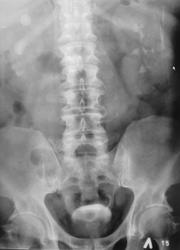

Пациент с диагнозом "МКБ" направлен на обзорную рентгенографию почек и мочевыводящих путей.

Пациент с диагнозом "МКБ" направлен на обзорную рентгенографию

Внутривенная урография.

На мой взгляд дополнительная интенсивная тень лежит за контуром почки. В проекции Желчного пузыря. Так что желчекаменная болезнь? Рекомендованно УЗИ печени и желчного пузыря.

Да с камнем желчного то все понятно...но вот тень в проекции н\трети правого мочеточника ....весьма необычна...вопрос - куда ее "пристроить"?))))

Да, камешек для желчного типичный.

А тень в дистальной трети мочеточника действительно "фердиперсовая"...